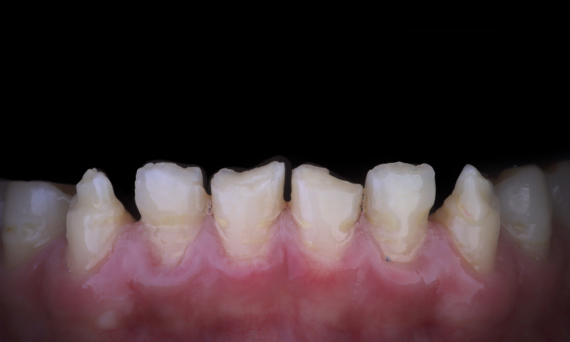

Before: The treatment objective was to rehabilitate the anterior maxilla and mandible for esthetic improvement. The clinical diagnosis revealed ameloenesis imperfecta.

After: Labside- fabricated restoration made from advanced lithium-disilicate ceramic CEREC Tessera and for the high esthetic result, the veneering with Celtra Ceram.